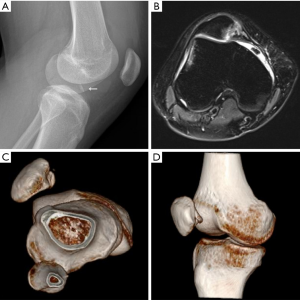

A medial parapatellar incision was made to identify the fracture fragment, and it was then reduced to the main body of the patella. A 2.0 mm Kirschner wire was drilled through the middle of the fragment. Six holes were then similarly made by 1.0 mm Kirschner wire around the fracture fragments, and each location was optimally selected. The distances between the holes and fracture edges were 2.0 mm. The PDS suture (Ethicon Inc., NJ, US) penetrated into the holes by spinal needle, and was then fixed and knotted in the back of the patella (Figure 1). The joint capsule and the medial retinaculum were repaired with appropriate tension.

Each patient had two-viewed X-ray (Figure 2A), CT, and MR exams preoperatively. MRI showed lateral femoral condylar bone marrow edema and MPFL lesions (Figure 2B). Computer tomography reconstruction images were also available for further diagnosis of the OCFs (Figure 2C,D). All 18 patients underwent X-ray (Figure 3) and MRI examinations postoperatively. Postoperative MRI showed the fixation fracture fragments and the image of drill channels (Figure 4). All of them showed good healing of the OCFs. However, the MRI showed that 4 patients had anterior patellar bursa with no clinical symptoms. There were small areas of cartilage thinning but no obvious sign of joint degeneration.